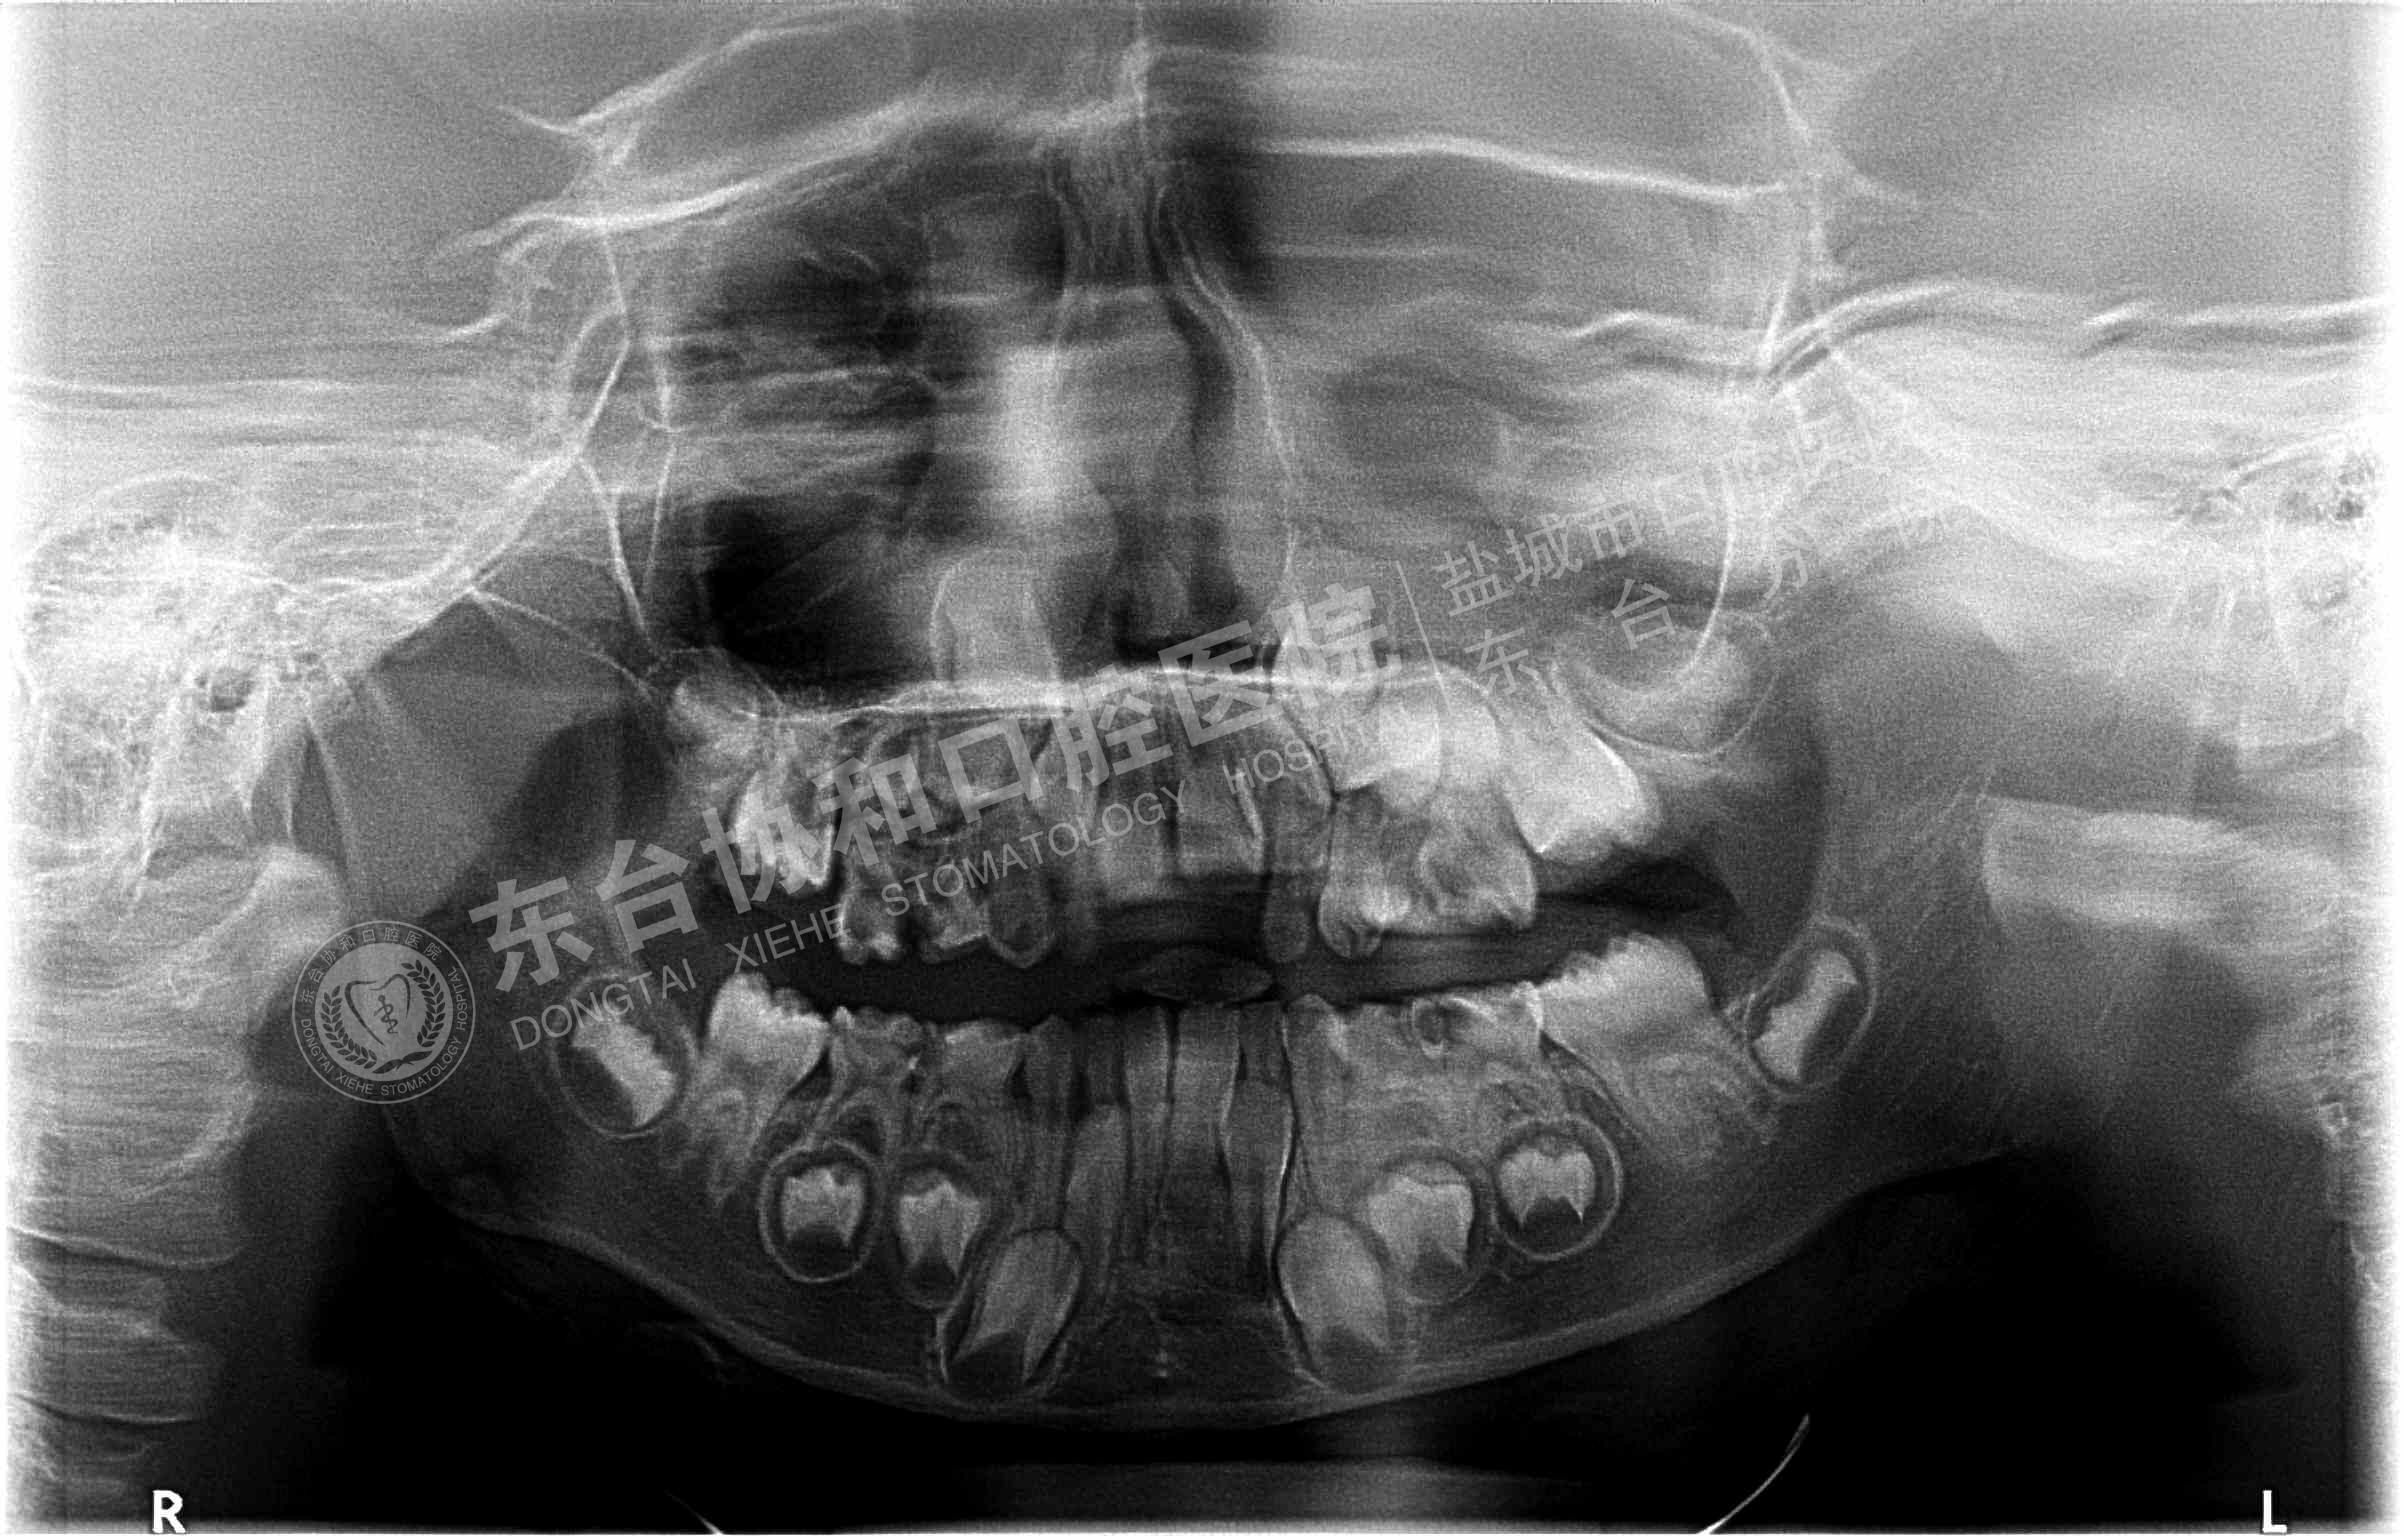

很多患者都很排斥拍牙片,認(rèn)為醫(yī)院是為了多收錢(qián)才讓他們拍的,其實(shí)這是一個(gè)錯(cuò)誤的想法,拍牙片是口腔科常用重要的檢查手段,臨床檢查只能直觀判斷牙冠和牙齦部分的情況,而對(duì)于牙根,牙槽骨、牙周膜等情況則必須通過(guò)牙片檢查。牙齒在牙片上顯示出白色阻射影像,其中牙釉質(zhì)阻射強(qiáng),牙本質(zhì)和牙骨質(zhì)阻射低于牙釉質(zhì),牙髓腔呈灰黑色影像,根管口至根尖孔呈逐漸變細(xì)的影像。

通過(guò)牙片除了了解牙齒的病變情況,還可以了解牙槽骨內(nèi)是否有埋伏牙、多生牙、牙源性腫瘤和囊腫等,依據(jù)牙片綜合分析可以提高牙齒診斷調(diào)節(jié)的準(zhǔn)確性和。

7、牙片來(lái)確定乳牙和恒牙的相對(duì)位置,用來(lái)幫助醫(yī)生診斷乳牙是否能自行脫落還是需要拔除。

8、牙齒矯正:拍攝口腔全景片和頭顱側(cè)位片,以檢查骨骼和牙齒的發(fā)育情況。